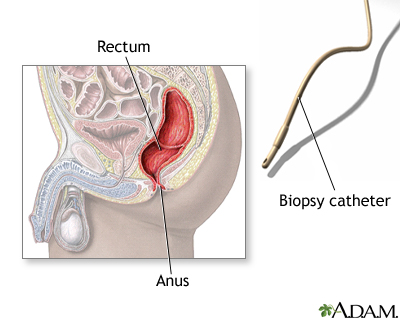

- Your health care provider gently places a gloved and lubricated finger into your rectum to check for blockage and gently enlarge (dilate) the anus. This is called a digital rectal exam.

- Next, the flexible sigmoidoscope is placed through the anus. The scope is a flexible tube with a camera at its end. The scope is gently moved into your colon. Air or carbon dioxide is inserted into the colon to enlarge the area and help the provider view the area better. The air may cause the urge to have a bowel movement or pass gas. Suction may be used to remove fluid or stool.

- Your provider may take tissue samples with a tiny biopsy tool or a thin metal snare inserted through the scope. Heat (electrocautery) may be used to remove polyps if your colon has been properly prepared for this. Photos of the inside of your colon may be taken.

Sigmoidoscopy using a rigid scope may be done to treat problems of the anus or rectum but is not used to screen for colon cancer.